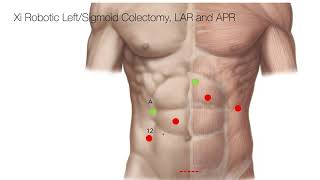

Port positions for Robotic LAR and ISR video

Port positions for Robotic LAR and ISR

Ports placement in lap. and robot liver resection Trocar Placement Robotic Left/Sigmoid Colectomy

Trocar Placement Robotic Left/Sigmoid Colectomy Intra-Corporeal anvil placement - Robotic LAR